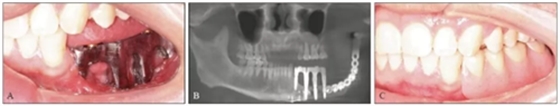

卸下患者口內(nèi)的35~37臨時(shí)個(gè)性化復(fù)合基臺(tái)保護(hù)帽和34復(fù)合基臺(tái)保護(hù)帽,注射生理鹽水沖洗種植體及周圍軟組織,口內(nèi)試戴純鈦鑄造桿(圖15A),拍攝CBCT示鑄造桿與種植體復(fù)合基臺(tái)對(duì)接良好(圖15B)。將34~37膠托活動(dòng)義齒就位于鑄造桿上部Locator附著體,囑患者做正中咬合及側(cè)方咬合,調(diào)磨咬合高點(diǎn),拋光,完成最終修復(fù)體的戴入(圖15C、D)。囑修復(fù)后修復(fù)體及牙周維護(hù)。